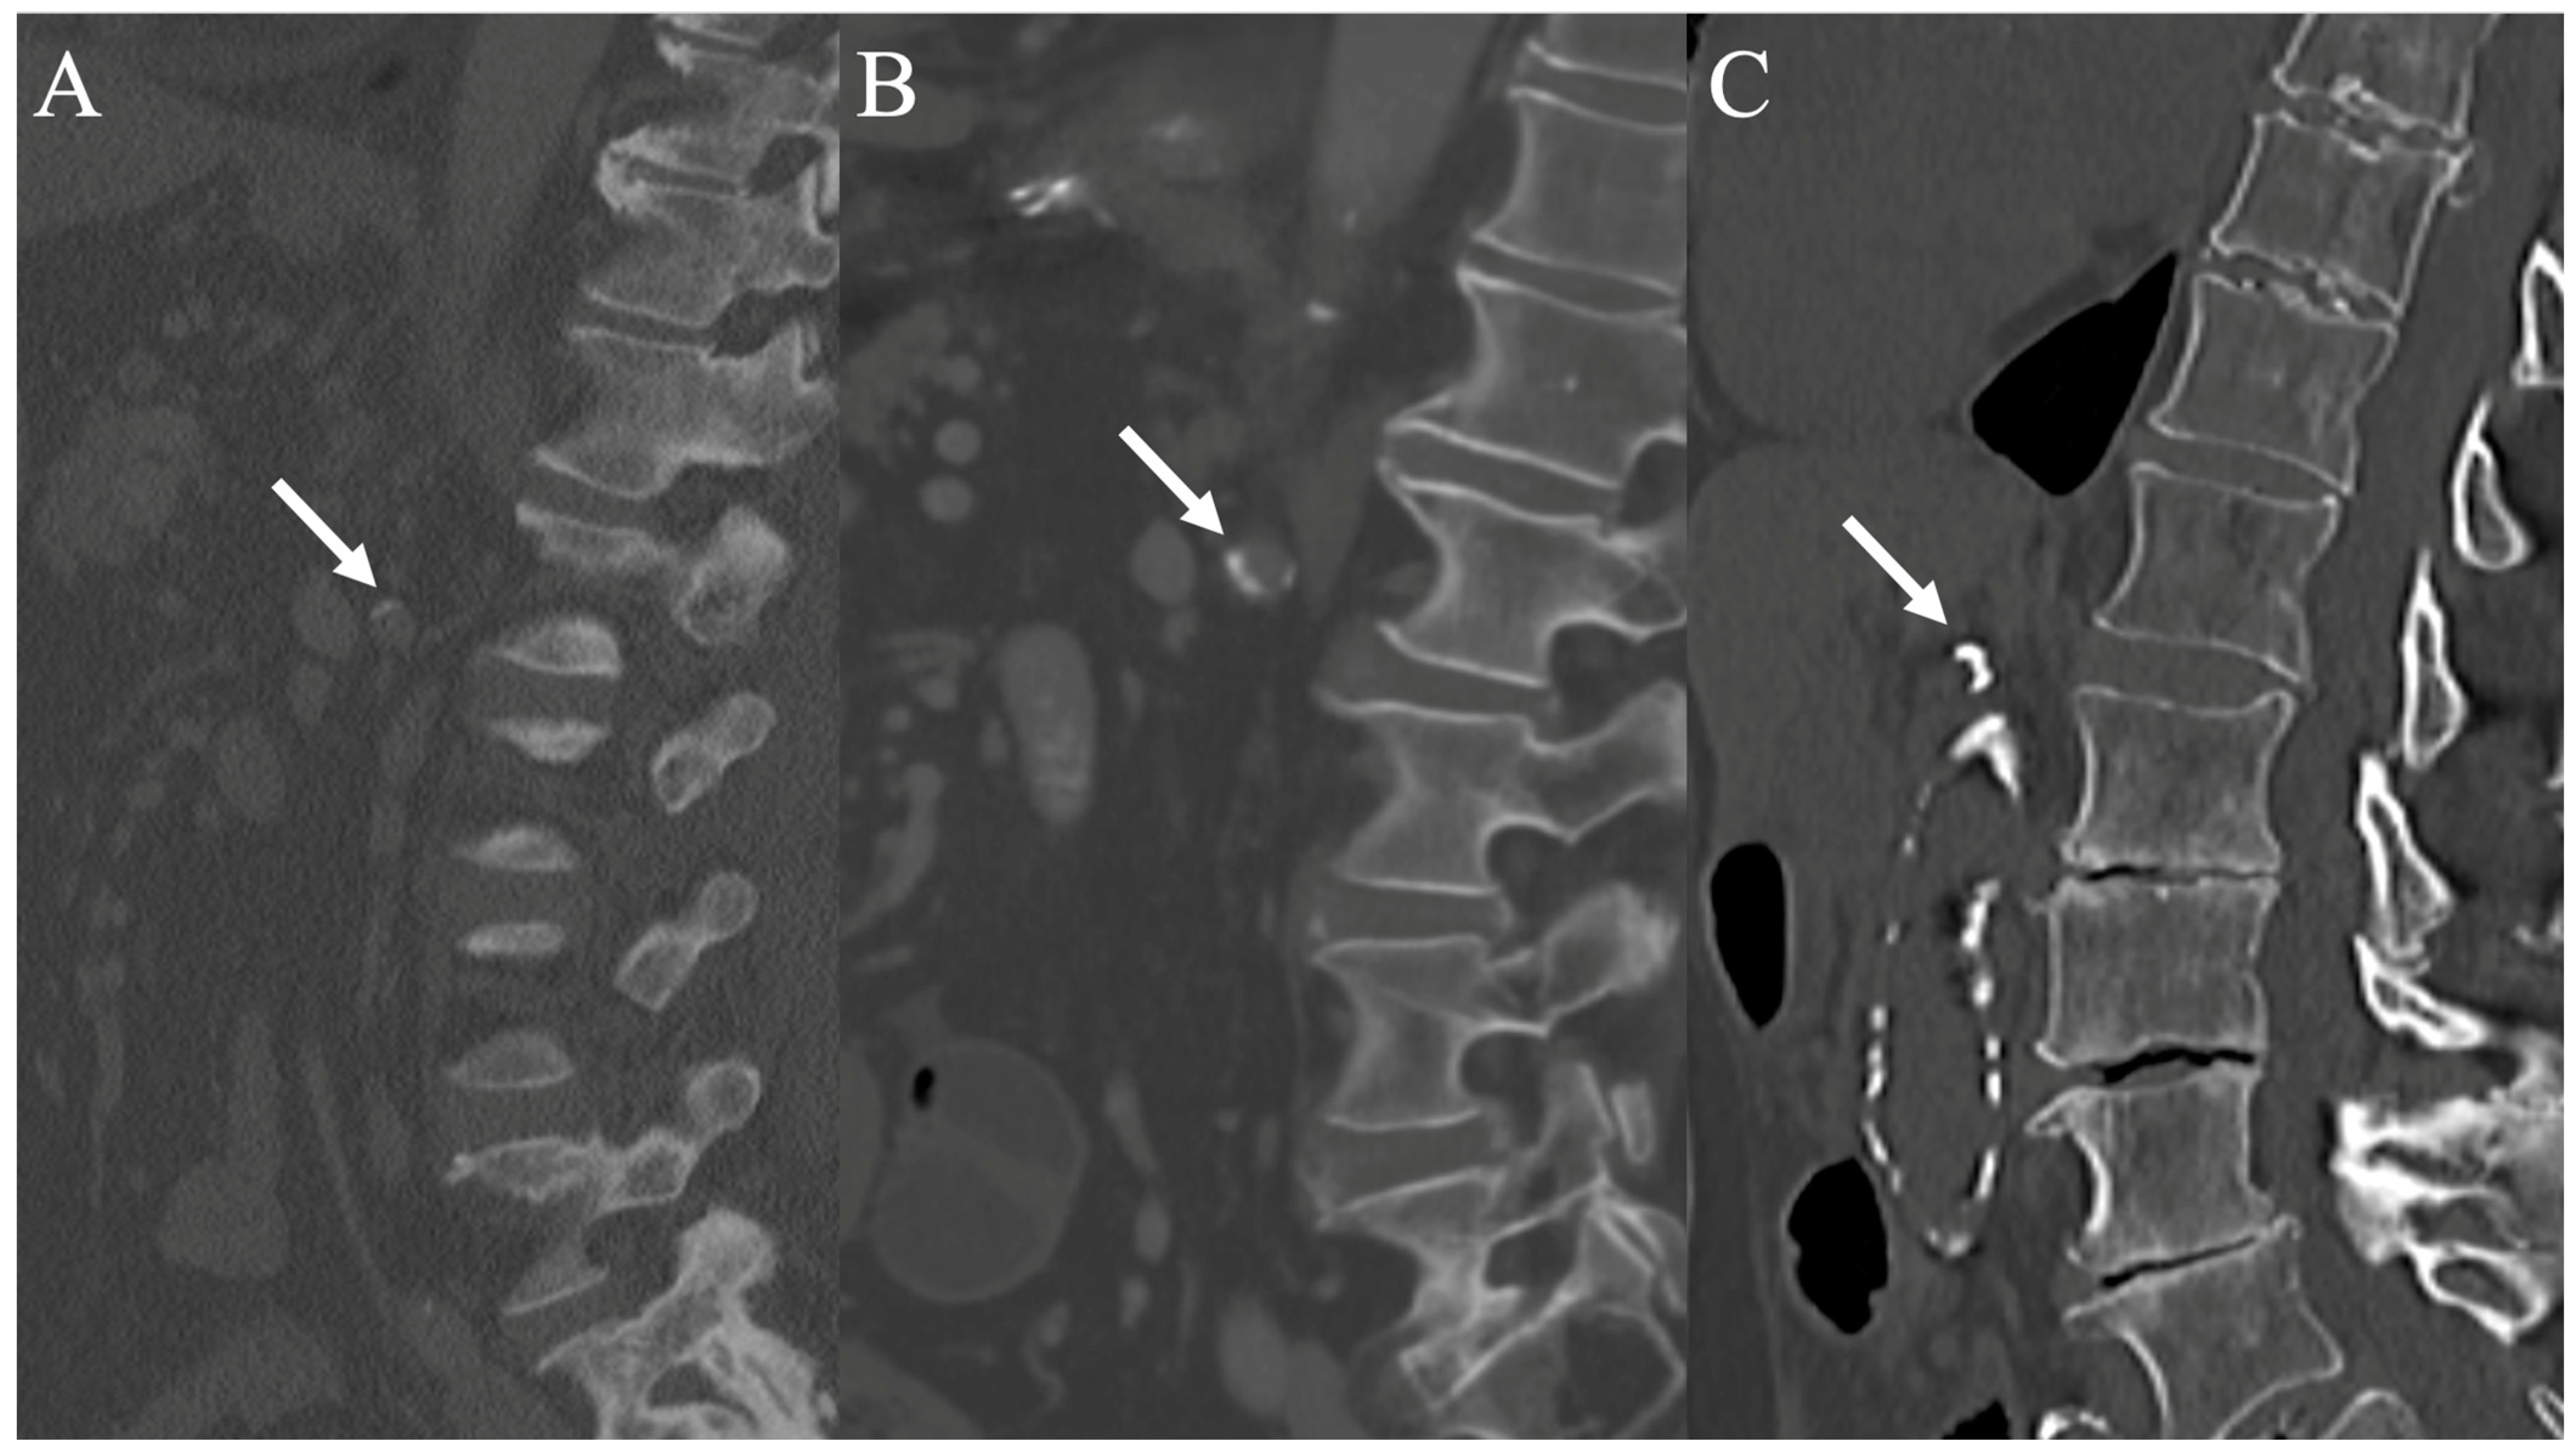

2.8. Radiological Analysis and Measurements